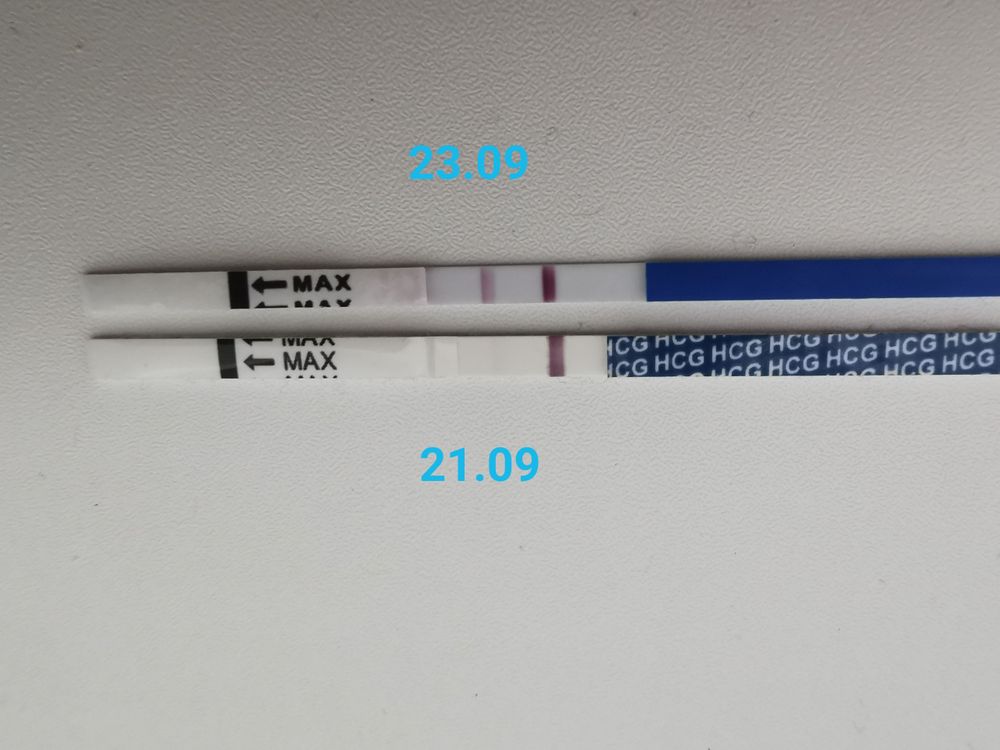

🌿15 тестов на беременность 🤦♀️🙆♀️